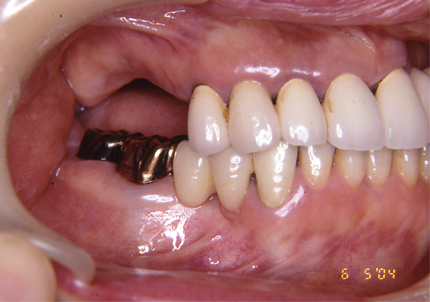

1.初診時(2006年5月)

2.上顎補綴物除去

3.上顎補綴物除去、旧インプラント除去手術後(骨吸収後)

5.仮歯装着歯装着

10.上顎補綴物装着(2008年12月)

12.上顎補綴物装着(2009年5月)

13.下顎補綴治療開始(2016年1月9日)

14.インプラント埋入(2016年8月24日)

15.右下6番近心根抜歯(2016年12月12日)

↑術後1か月(2017年1月7日)

16.下顎インプラント補綴治療終了(2017年4月8日)